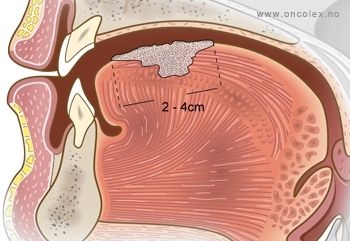

T2: Svulster på 2-4 cm i største diameter.

- T2 – svulster på 2-4 cm i største diameter